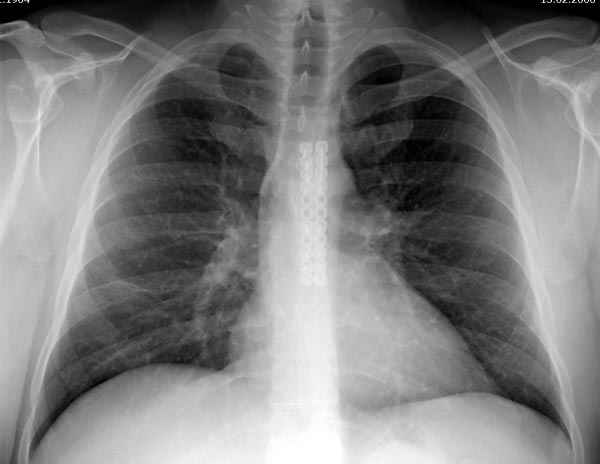

[Ortho] несращение грудины

В большинстве ложные суставы грудины встречаются в практике кардиохирургов, а в поле зрения ортопедов попадают совершенно случайно; в междисциплинарных консультациях или кто-то из знакомых, когда имеют проблему после кардиологических вмешательств. Интересно отметить, что в отличие от ортопедических больных кардиологические больные очень редко жалуются на работу хирурга. Дискомфорт в области грудины большинство принимают за малую проблему, и если обращают внимание, тогда терапию заканчивают назначением анальгетиков.

В образовании ложного сустава имеет значение метод фиксации, и проволочная фиксация уступает современным имплантам для плоских костей. При беседе с кардиохирургами выяснилось, что ложный сустав развивается в основном из-за прорезывания фиксирующего материала, а также из-за раневой инфекции. Поэтому многие кардиохирруги отошли от традиционных методов и перешли к современным имплантам. Вместе одиночных швов накладываю,т "восьмерку" проволокой или применяют различные пластины.

Мой опыт небольшой, и один из случаев выставлял на Ортофорум пару лет назад. Те ложные суставы, которые  пришлось наблюдать, несмотря на малую подвижность, имели более выраженный болевой синдром, и симптомы проходили после создания стабильности. Фиксацию посттравматического ложного сустава провели совместно с торакальным хирургом установкой двух пластин Synthes 2.4 мм, применяемых в челюстно-лицевой хирургии. Блокировка получилась за счет однокортикальных коротких шурупов, которые создали профилактику пенетрации сверлом в средостение.